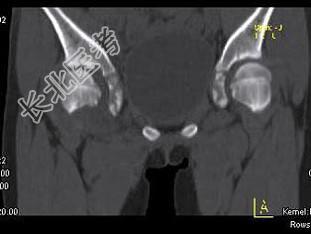

- 单项选择题女,11岁, 肺部有结核病史,二个月前右髋关节有外伤史, 右髋关节部逐渐肿胀疼痛,休息后可减轻, 结合图像,最可能的诊断是 ( )

A、右髋关节结核

B、化脓性关节炎

C、右髋关节退行性变

D、右髋关节类风湿关节炎

E、右髋关节痛风